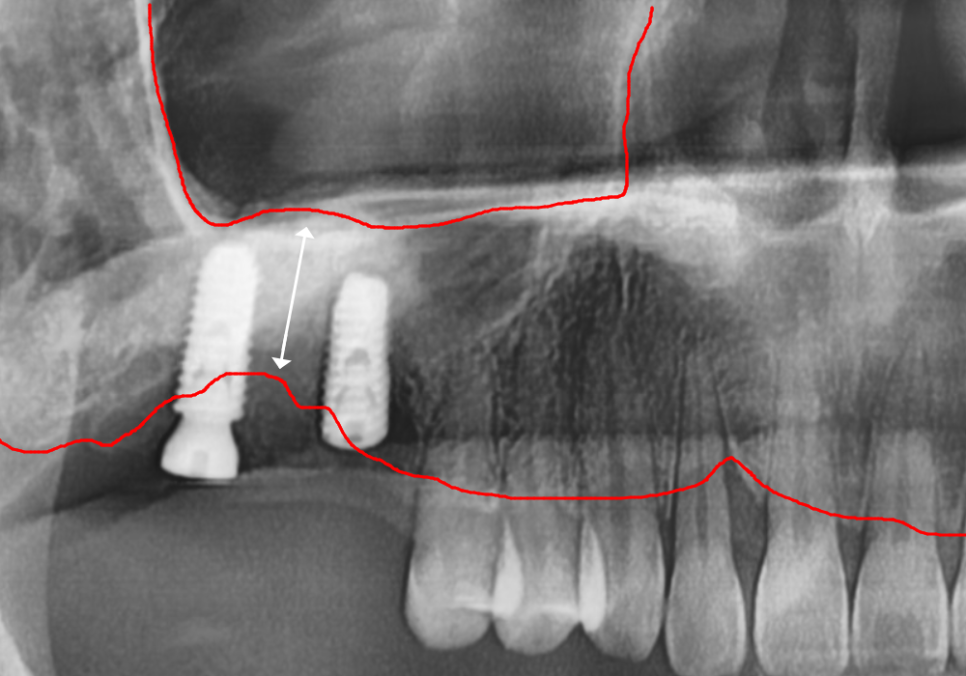

240517

"뼈이식 양이 왜 이렇게 많나요?"

간혹 이식된 양을 보고 과한 것 아니냐고

의아해하시는 분들도 계시지만,

이는 뼈가 굳으면서 조금씩 흡수될 양까지

미리 계산한 '보상 이식'입니다.

추후 부작용이나 재수술 없이

한 번에 튼튼하게 끝내기 위한

과정이라고 생각하시면 됩니다. ^^

뼈가 단단하게 굳기를

약 3개월간 기다린 후,

임플란트 고정체를 식립했습니다.

240608

뼈가 잘 자리 잡은 덕분에

아주 안정적으로 고정되었죠.

물론 여기서 또 한 번의 기다림이 필요합니다.